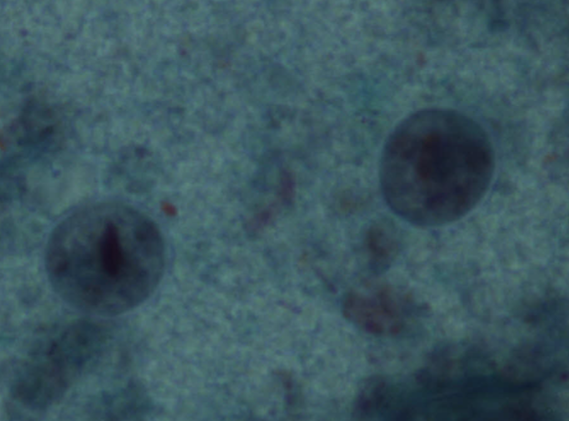

Entamoeba histolytica - Pełzak czerwonki - Cysta